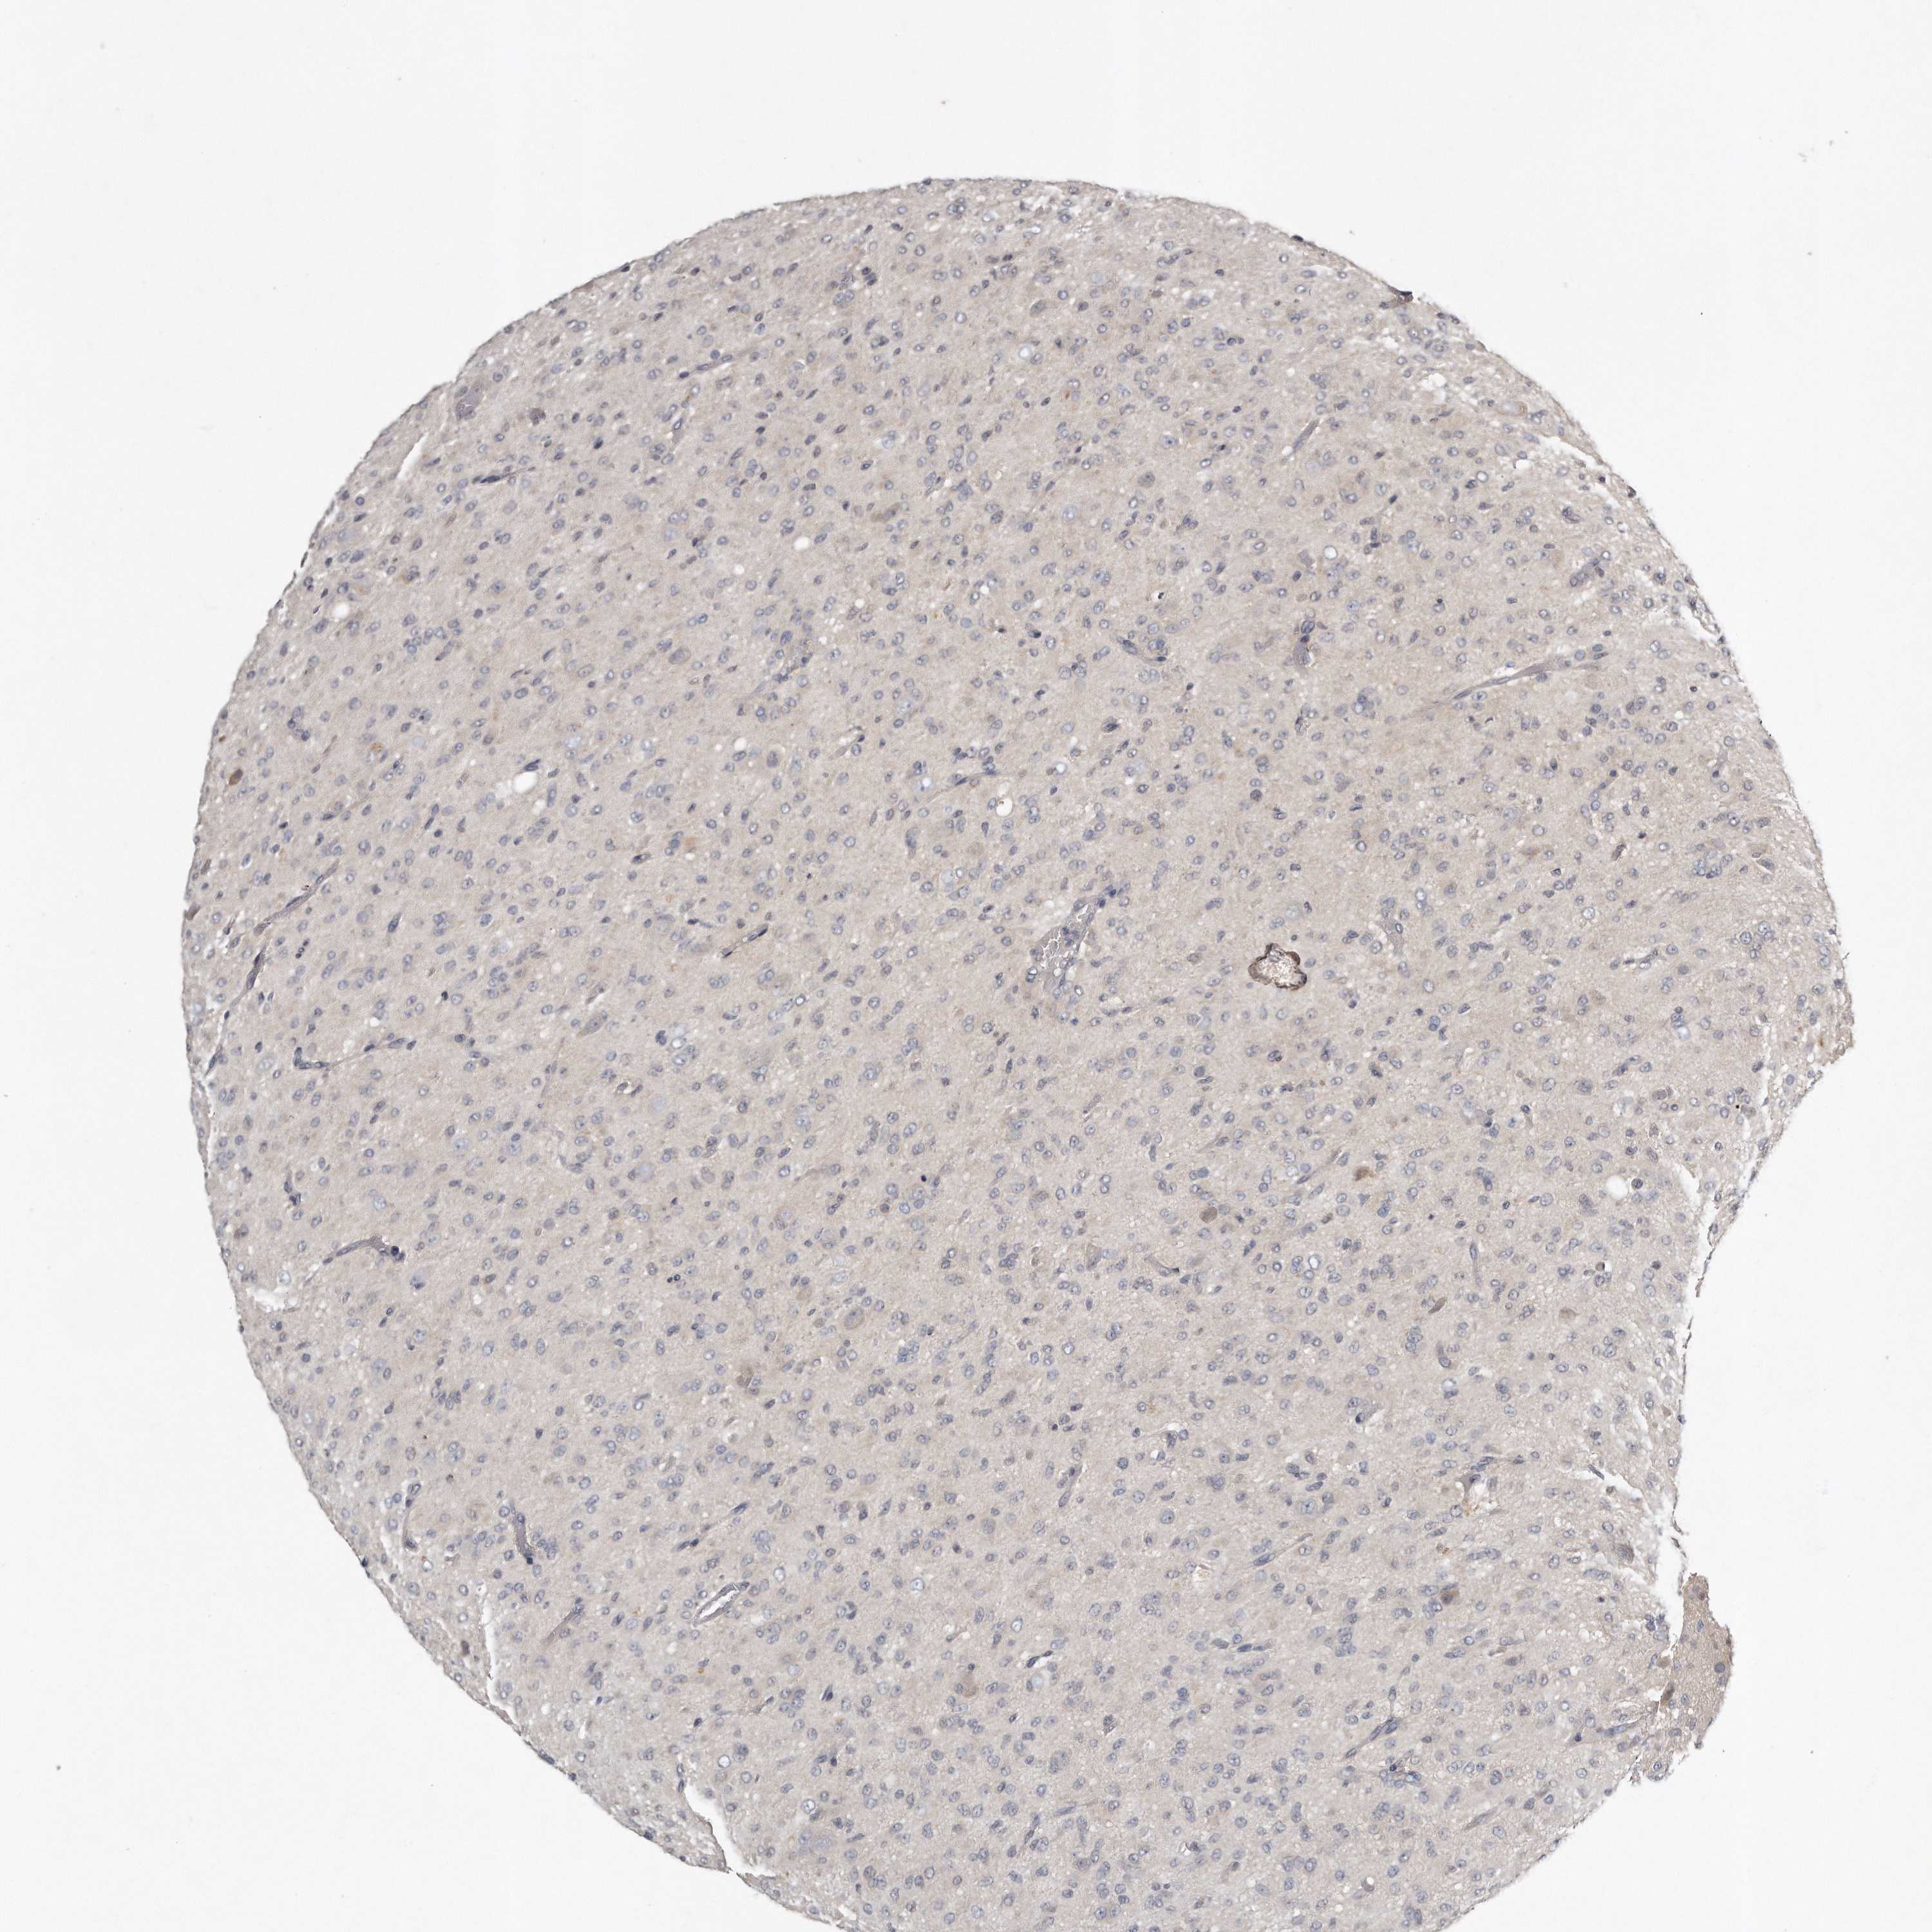

GLIOMA - Protein expressioni

A mouse-over function shows sample information and annotation data. Click on an image to view it in a full screen mode. Samples can be filtered based on level of antibody staining by selecting one or several of the following categories: high, medium, low and not detected. The assay and annotation is described here.

Note that samples used for immunohistochemistry by the Human Protein Atlas do not correspond to samples in the TCGA dataset.

Antibody stainingi

Antibody staining in the annotated cell types in the current human tissue is reported as not detected, low, medium, or high, based on conventional immunohistochemistry profiling in selected tissues. This score is based on the combination of the staining intensity and fraction of stained cells.

Each image is clickable and will lead to virtual microscopy that enables deeper exploration of all samples and also displays staining intensity scores, fraction scores and subcellular localization as well as patient and tissue information for each sample.

Antibody HPA020735

Antibody HPA029914

Staining

High

Medium

Low

Not detected

Intensity

Strong

Moderate

Weak

Negative

Quantity

>75%

75%-25%

<25%

None

Location

Nuclear

Cytoplasmic/membranous

Cytoplasmic/membranous,nuclear

Glioma, malignant, High grade

Glioma, malignant, Low grade

Glioblastoma, NOS